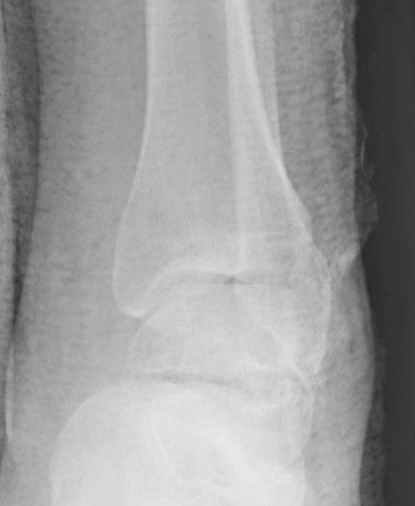

За пару недель насчитал 5 больных с переломом таранной кости, из них двое с двусторонним повреждением.

Из-за отека на стопе тактика лечения у всех была

одинаковая: временная наружная фиксация до спадения отека, при изолированных переломах они выписывались домой и через дней 7 госпитализировались на оперативное лечение.

Примеры на снимке...